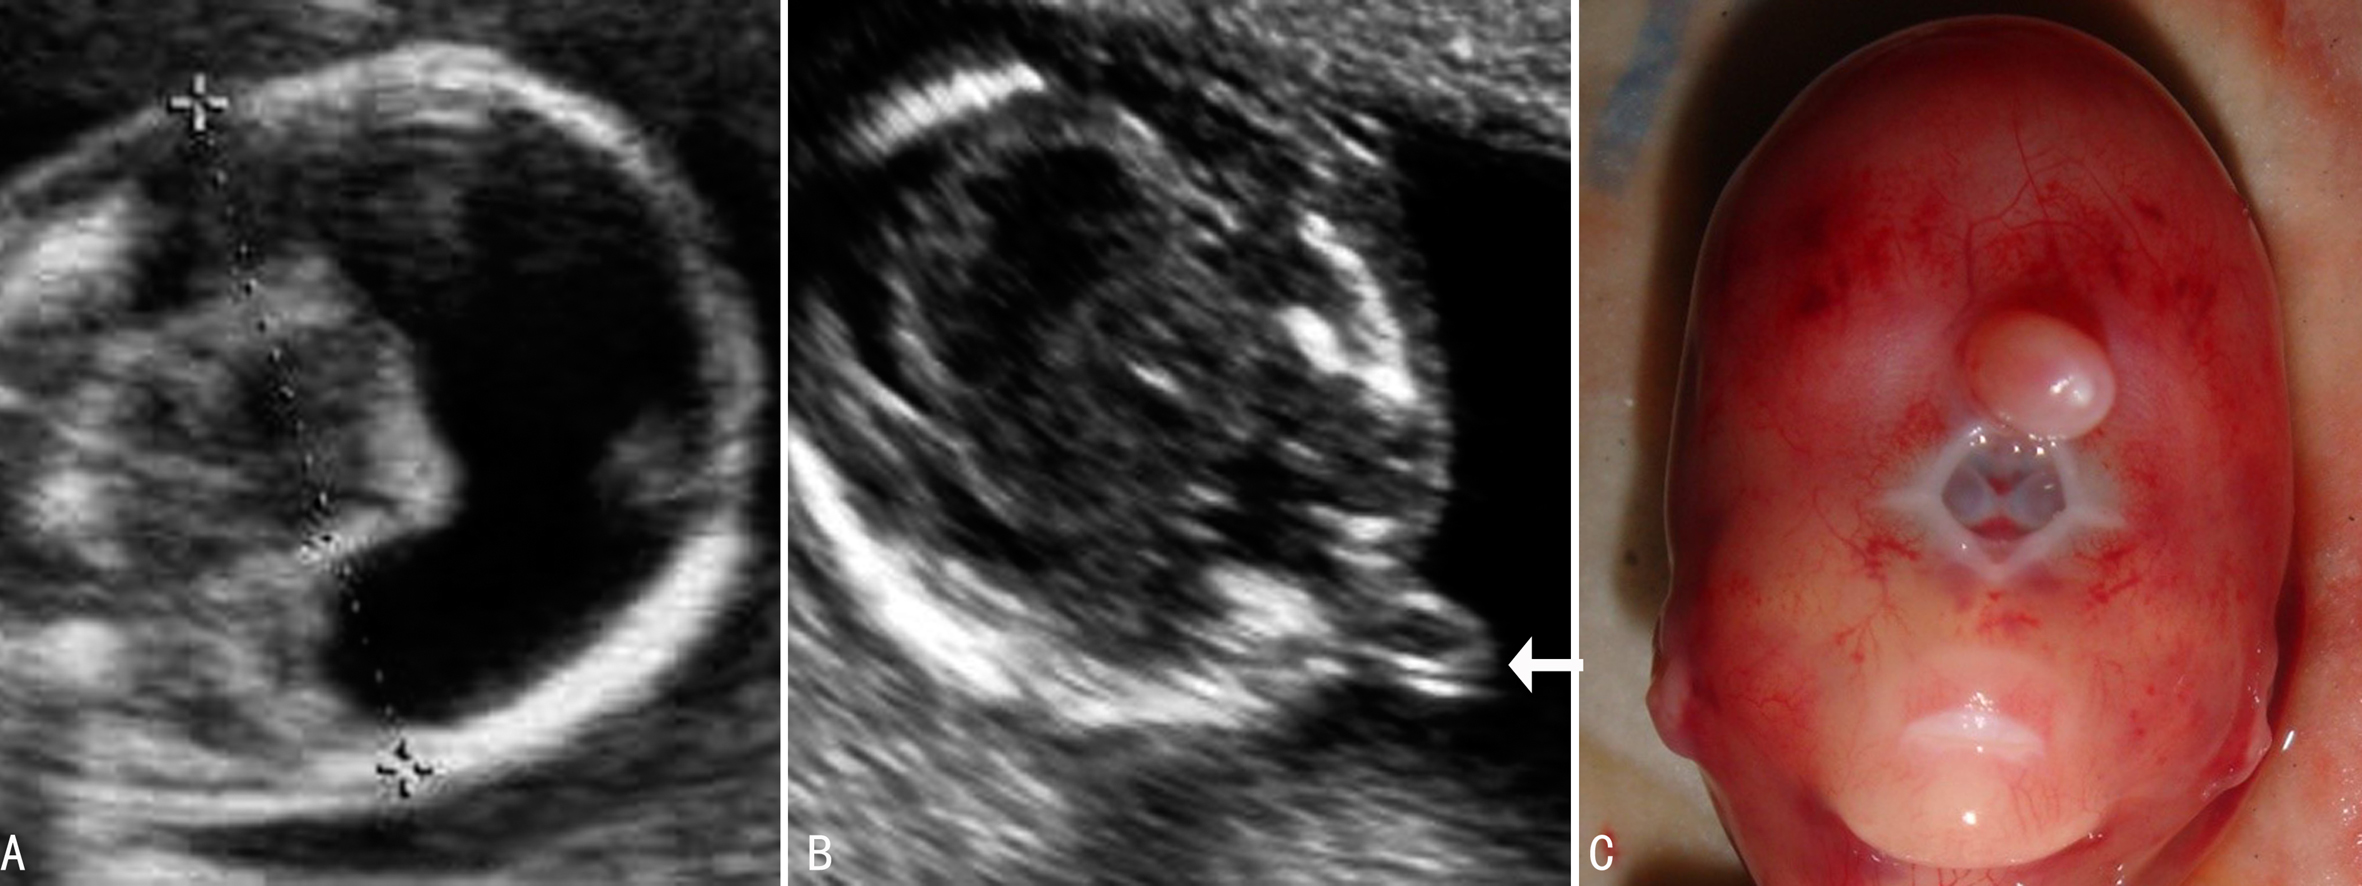

图2无叶全前脑畸形

2.超声检查 小头、单一脑室、无第三脑室、无透明隔、无胼胝体、无脑中线、丘脑窄小、融合等为本型超声检查特点。头型为短头状,单一的脑室常常是发现前脑无叶无裂畸形的线索。脑室腔左右相通,缺乏中线结构回声或显示不完整的中线样回声,脑组织可呈现盘状、杯状和球状。严重时颅内回声紊乱导致颅内结构的辨认困难。“背侧囊肿”显示为颅盖与大脑皮层之间的囊状无回声,脑内旋越差,背侧囊肿越大,脑皮质组织就越少。伴发的面部结构异常包括眼间距过小,严重者独眼,有时见两个眼球紧靠在一起位于一个眼眶中;无鼻、单鼻孔或者喙鼻(图2);中央性唇裂或同时伴发腭裂。